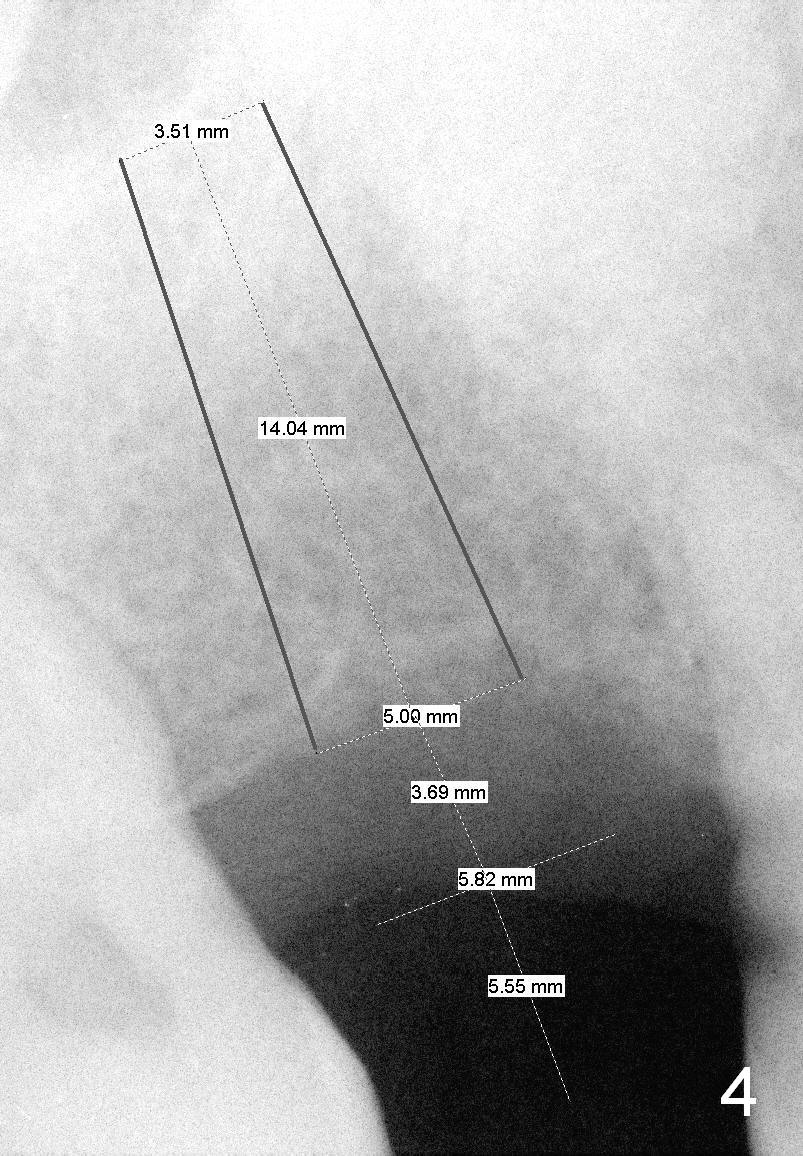

A 63-year-old man has lost the tooth #3 for long time: the first PA taken in our office is 5 years ago (Fig.1) before the tooth #5 received root canal therapy (Fig.2). The mesiodistal space of the edentulous is narrow, 8 mm (Fig.1) as compared to 10-11 mm for normal space.